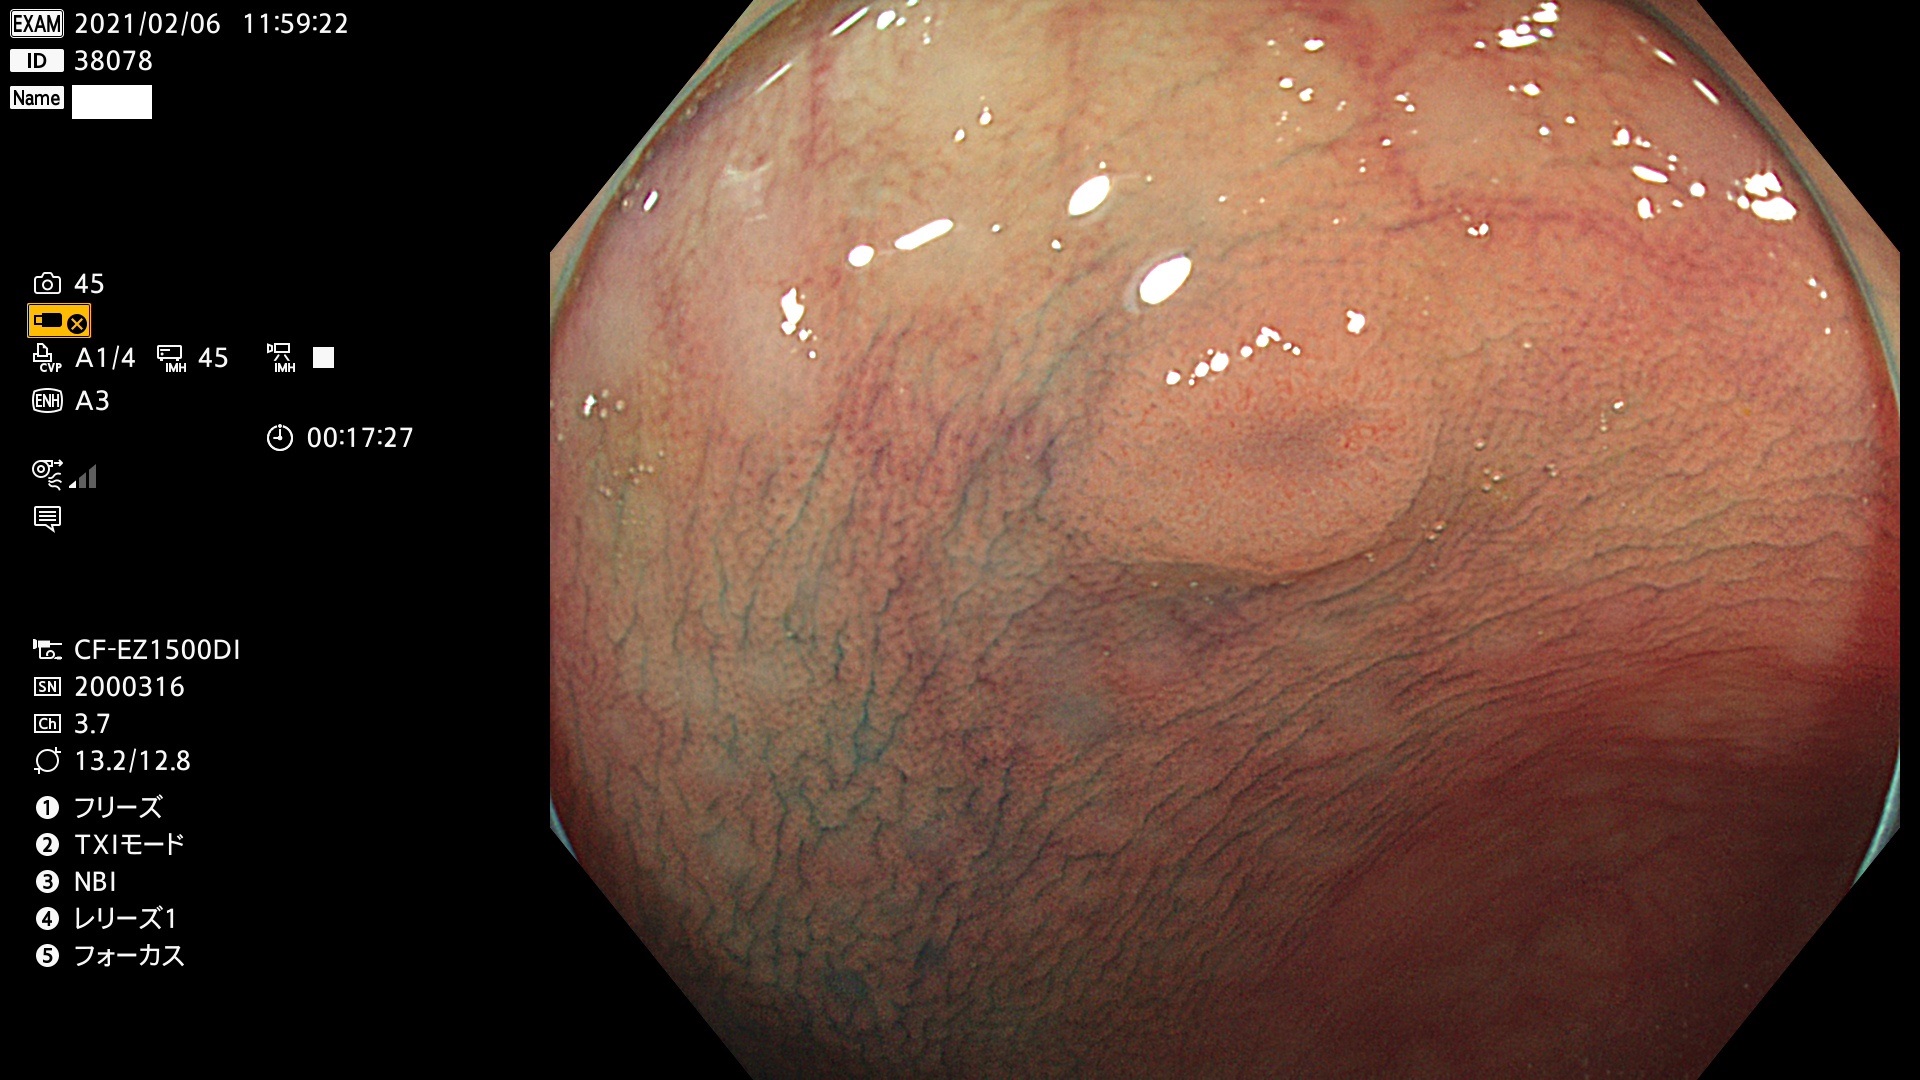

38001 38002 38003 38004 38006(SSAPのみ) 38007 38008 38009 38010 38012 38013 38014 38016 38018 38020 38021 38025 38026 38029 38032 38033 38034 38035 38036 38037(SSAPのみ) 38039 38043 38044 38048 38049 38050 38052 38055 38056 38057 38058 38059 38064(SSAPのみ) 38065 38068 38069 38070 38071 38072 38074 38075 38076 38078 38079 38080 38082 38083 38084 38085(SSAPのみ) 38086 38087 38088 38089 38090 38091 38092 38093 38094 38097 38098 38099

発見困難で危険性の高い平坦型病変(上記100名より抽出)